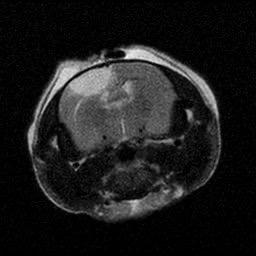

Figure 2. (A-B) Representative MRI images showcasing the lesioned brain area ofChrdl1 Ckoand Cre(-)mice at1daypost-stroke and 7days post-stroke. (C) Bar graph comparison of stroke volume between Cre (-) andCkomice,1dayand7dayspoststroke.Statisticaldifferencesbetween groups or time points, where applicable, are indicated by asterisks (*p< 0.05, **p<0.01). (D) Line graph comparison of stroke area percentage betweenCre(-)andCkomice,1dayand7dayspoststroke.